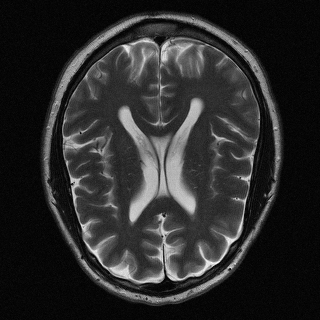

This article presents a novel undersampled magnetic resonance imaging (MRI) technique that leverages the concept of Neural Radiance Field (NeRF). With radial undersampling, the corresponding imaging problem can be reformulated into an image modeling task from sparse-view rendered data; therefore, a high dimensional MR image is obtainable from undersampled $k$-space data by taking advantage of implicit neural representation. A multi-layer perceptron, which is designed to output an image intensity from a spatial coordinate, learns the MR physics-driven rendering relation between given measurement data and desired image. Effective undersampling strategies for high-quality neural representation are investigated. The proposed method serves two benefits: (i) The learning is based fully on single undersampled $k$-space data, not a bunch of measured data and target image sets. It can be used potentially for diagnostic MR imaging, such as fetal MRI, where data acquisition is relatively rare or limited against diversity of clinical images while undersampled reconstruction is highly demanded. (ii) A reconstructed MR image is a scan-specific representation highly adaptive to the given $k$-space measurement. Numerous experiments validate the feasibility and capability of the proposed approach.